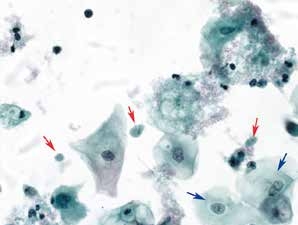

图2-13 阴道滴虫(高倍、液基、巴氏染色)

成群的滴虫(红箭头)以及炎性背景,鳞状上皮细胞反应性胞核增大。

图2-14 阴道滴虫(高倍、液基、巴氏染色)

滴虫(红箭头)梨形或椭圆形。核偏位,梭形或椭圆形。最下方滴虫具有明显的鞭毛。鳞状上皮细胞反应性改变,核周小空晕。

图2-15 阴道滴虫(高倍、液基、巴氏染色)

滴虫(红箭头)核呈明显的梭形,嗜碱性。鳞状上皮细胞反应性改变,背景污秽。插图示多量形态各异的滴虫。

滴虫(中间红箭头)、细胞碎屑(右侧红箭头)、鳞状上皮细胞反应性改变,核周小空晕(蓝箭头)。

图2-19 阴道滴虫(高倍、液基、巴氏染色)

滴虫(红箭头)形态各异,鳞状上皮细胞(蓝箭头)反应性改变,核周小空晕,胞质嗜双色性。炎细胞较多,背景污浊。

阴道滴虫是一种寄生虫性的性传播疾病。细胞形态特征:滴虫多呈倒置的梨形、椭圆形或圆形,中央可见一个梭形的核,有时核偏位或贴边,染色浅,嗜碱性。胞质灰蓝色伴有嗜伊红染颗粒,液基制片有时可见鞭毛(传统涂片一般不能发现)。多伴急性炎性背景,背景较污秽,细胞胞质腐烂,多碎屑,嗜双色性,退变,可见核周小空晕。

滴虫散在多量出现,极少单独出现。若能见到清晰的核、嗜伊红染的胞质颗粒或清晰的鞭毛,可以判读为滴虫。清晰的核是诊断滴虫的必要条件。鉴别:退变的白细胞、细胞碎屑、萎缩性上皮细胞。